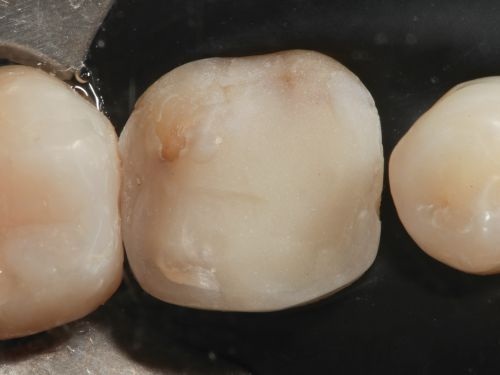

A 35-year-old male presented to the clinic to replace some inadequate restorations, one of which was for the lower right first molar (Fig. 1). For this tooth, the molar was restored with composite resin using the direct technique. The operative field was isolated, the old restoration was removed, and surface hybridization was completed using Futurabond U universal adhesive from Voco (Fig. 2). After placing a sectional matrix and a spacer ring, the composite resin (Voco’s GrandioSO 4U, shade A2) was placed in the proximal box with a thickness less than 4 mm, which is the maximum recommended thickness for the chosen material (Fig. 3). Additional increments of composite resin were applied to complete the anatomical stratification. The final morphology was sculpted, followed by light-curing to ensure complete polymerization (Fig. 4). The rubber dam was removed (Fig. 5), and the occlusion was adjusted using a finishing carbide bur with 12 blades (Fig. 6). Finishing and polishing was completed, with the final result shown in the Figures 7 and 8.